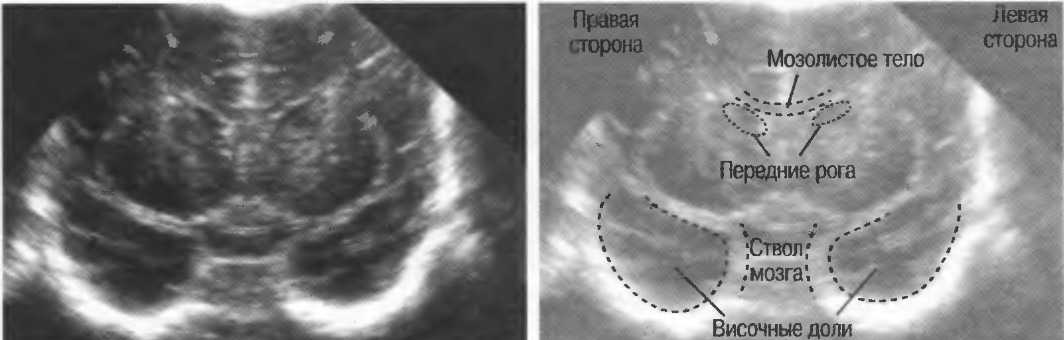

3. Ультразвуковые исследования в педиатрии. Для детей необходим датчик с частотой 5 МГц с глубиной фокусировки на 5-7 см. При исследовании мозга новорожденного используется секторный датчик с частотой 7,5 МГц с глубиной фокусировки на 4-5 см (этот датчик также используется для исследования яичек и структур шеи у взрослых).